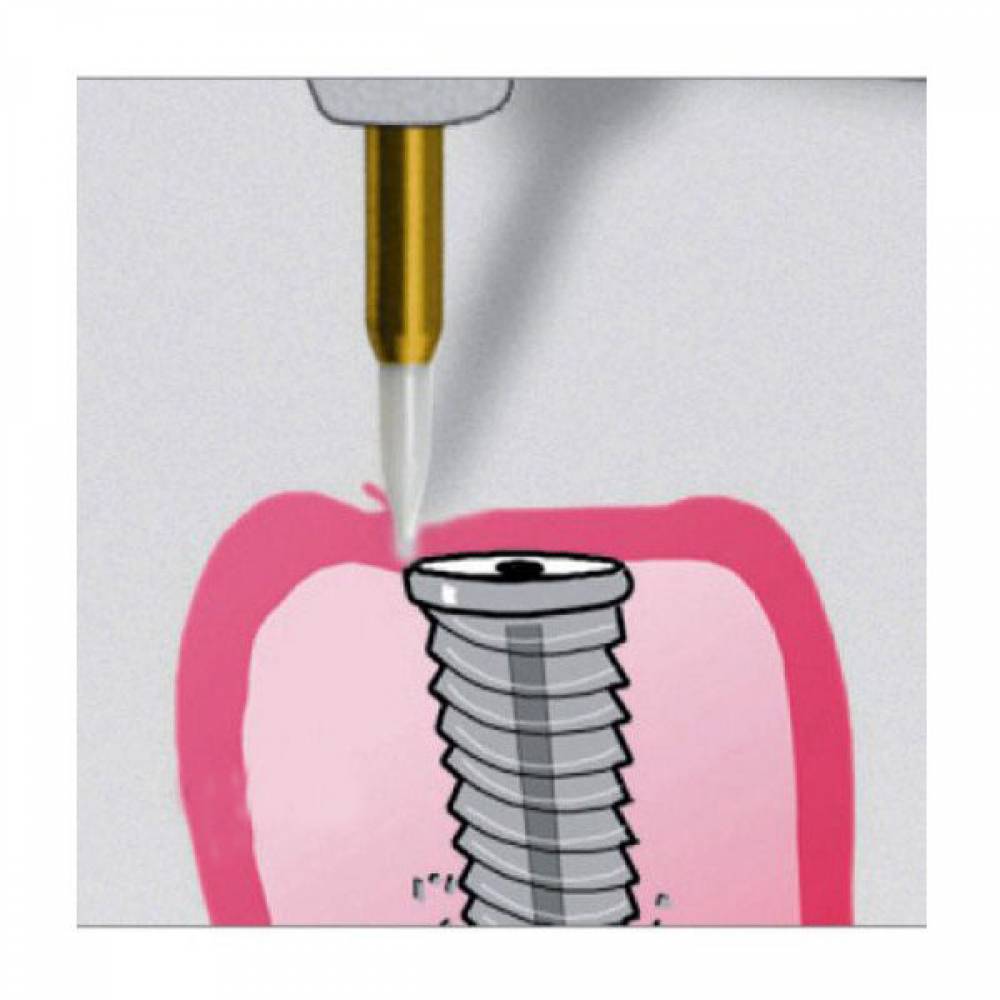

| کاربرد | برداشت لثه (Papilectomy) – برداشت بافت هاى مزاحم نشست روکش – باز کردن سالکوس قبل از گرفتن قالب – آشکار سازى بخش هاى از ایمپلنت که دیده نمى شود و دندانها نهفته |

| ویژگی ها | انرژى جنبشى در بافت نرم به حرارت تبدیل مى شود . |